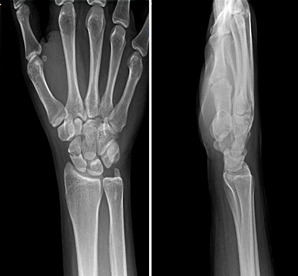

Röntgen: İlk gün çekilen röntgende kırık hattı bazen görülmez. Eğer şüphe varsa hasta 7-10 gün sonra tekrar röntgene çağrılır. En güzeli MR veya BT çektirilir.

BT ve MR: Şüpheli durumlarda veya kırığın yer değiştirmesini (deplasman) görmek için Bilgisayarlı Tomografi (BT) en net sonucu verir. Manyetik Rezonans (MR) ise kemiğin kanlanmasını ve ödemi gösterir.

skafoidröntgen2